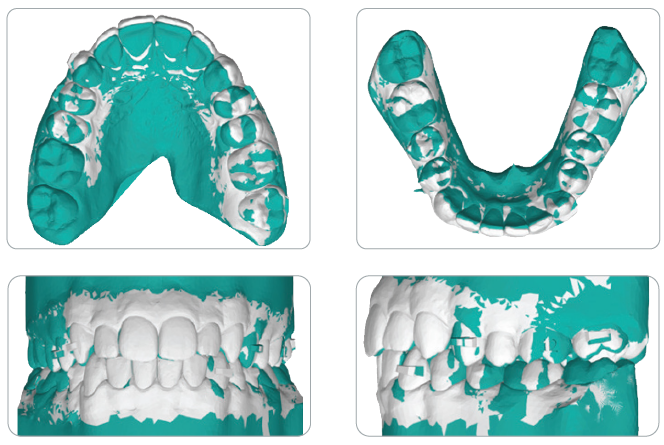

The clear aligner therapy lasted eight months. Treatment Results Post-treatment records indicated a satisfactory outcome after four months of Carriere Motion Appliance with fulltime Class II elastic wear and eight months of clear aligner therapy.

The patient showed an aesthetic profile and incisor display on smiling, along with a Class I canine and molar relationship. The midlines were centered and the crowding was resolved, but the second molar occlusal contacts were less than optimal, probably because of the presence of a palatal precontact. Post-treatment panoramic radiography evidenced good root parallelism with no sign of crestal bone height reduction or apical root resorption. Cephalometric analysis indicated that the inclination of the lower incisors with respect to the mandibular plane (IMPA) increased slightly, from 96.3° to 9.9°, demonstrating the anchorage control provided by the appliance (check Table 1 in the full article). Superimposition of the pre- and post-treatment cephalometric tracings, according to the method developed by Björk,9,10 highlighted a clockwise rotation of the occlusal plane. The appliance’s control of the vertical height and lower-incisor proclination was clear from the regional superimpositions. Even though the treatment period was short, the superimpositions revealed considerable residual growth in a downward and forward direction, since the initial radiographs were taken six months before treatment began.